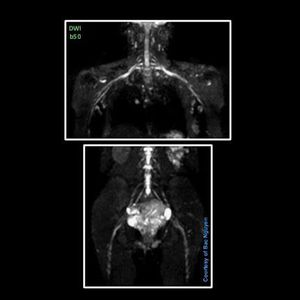

MRI Nerve Imaging – Single Shot EPI DWI @ Siemens 1.5T Aera DWI for visualizing nerves.#s_mri #siemens #mri #dwi